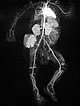

In the final control angiography with long series after injection into the right common iliac artery, the tumor is completely devascularized. The unaffected, physiological arterial branches of the surrounding tissue are all preserved. Thus, the tumor is completely eliminated from the circulation. Activation of coagulation and consumption of platelets in the tumor has stopped.

The clinical course was very encouraging. The volume of the tumor had already decreased immediately after embolization. Platelet levels rose rapidly, as did fibrinogen and coagulation factors. The Kasabach-Merritt phenomenon was suspended. This image 17 days after embolization shows the clinical success.

The typical clinical picture of a newborn with a reddish-bluish tumor immediately after birth, massive coagulopathy with spontaneous hemorrhage and marked thrombocytopenia is clearly indicative of a kaposiform hemangioendothelioma with Kasabach-Merritt phenomenon. In this case, mere substitution of platelets and coagulation factors is usually insufficient. Super-selective embolization while preserving the healthy arteries prevents intratumoral activation of coagulation and trapping of platelets across the massively perfused tumor. This was also very successful in this infant. Currently, the patient is on sirolimus and is developing very well without recurrence.